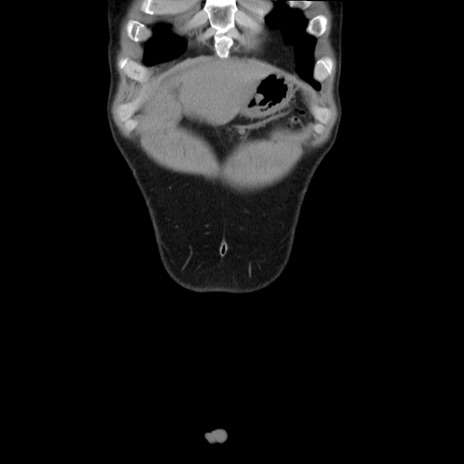

横断像